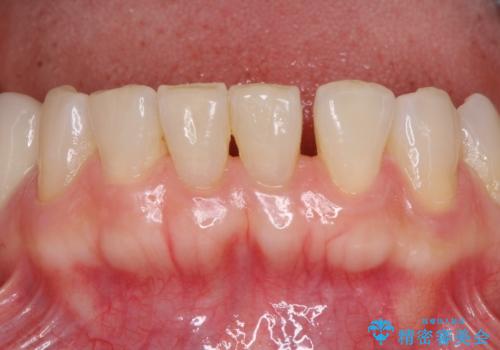

- 口の中に気になるところが沢山あるものの、地元ではなかなか治療を行ってくれるところがないとのことで、沖縄県の離島より来院された患者様です。

金属を使用した前歯のブリッジや奥歯の銀歯は全てオールセラミッククラウンまたはセラミックインレーとし、左下の奥歯はインプラントにより治療を行うこととしました。

外科処置を行うため、治癒を待つ期間が数ヶ月あるため、その期間を利用して下顎前歯のスペースを矯正治療で閉じることとしました。